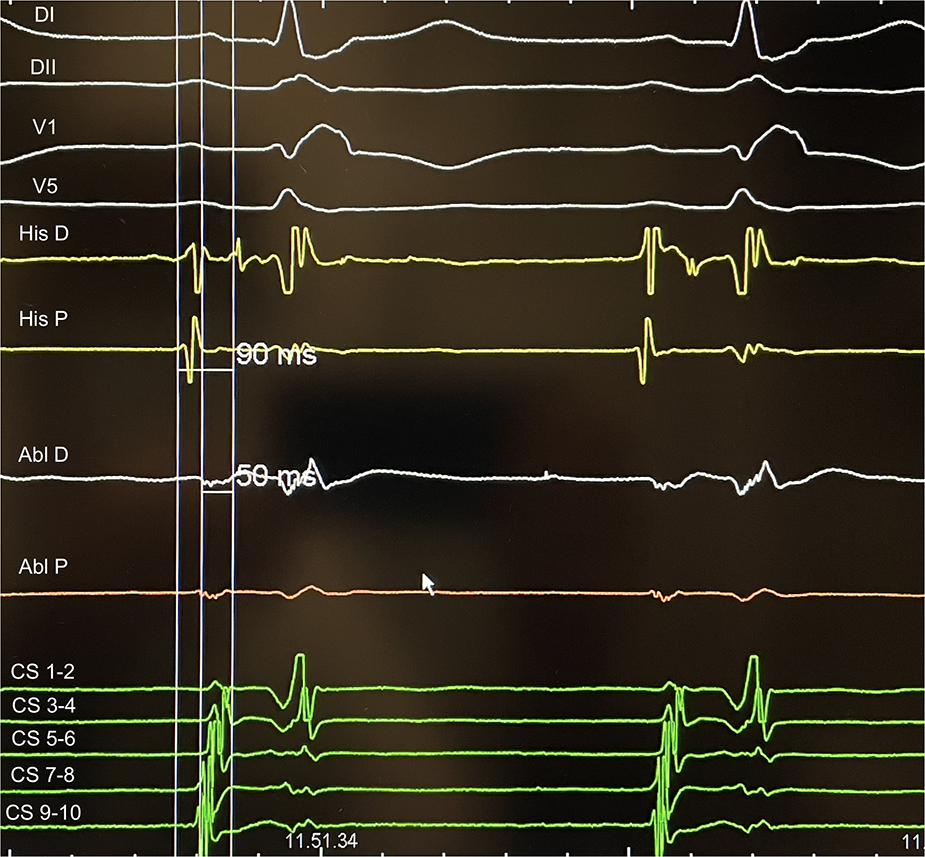

Once the diagnosis of AVNRT was established, the ablation catheter was moved from RV to Koch Triangle. In correspondence of Koch triangle's latest activation area identified with the techniques described above (Figure 1), a “hump and spike” signal (9, 10) was recorded during sinus rhythm, and the maximum local atrial-His delay (ms) and the local distance (mm) from the His bundle were evaluated (Figure 2). RF energy [power 30 W, not irrigated tip, temperature setting of 55°C, minimum contact force (CF) 5 g, up to 60 s] was delivered in correspondence to the latest activation area to obtain junctional beats with 1:1 retrograde ventriculo-atrial (VA) conduction. In case of absence of VA retrograde conduction during junctional rhythm, RF delivery was immediately interrupted. Once junctional rhythm with VA conduction was recorded, energy delivery was continued up to 60 s or until junctional rhythm cessation. Following ablation, arrhythmia induction at baseline and under isoproterenol infusion was attempted. End points for ablation success were non-inducibility of AVNRT and elimination of atrial-His jump; in case of modulation of slow pathway, single atrial-His jump eventually followed by single reentry was tolerated without tachycardia induction (6).

Figure 2

An example of AH measurement on His catheter and at the ablation site during slow pathway ablation: the difference represents delay of the local atriogram to His atriogram (40 ms in this case).